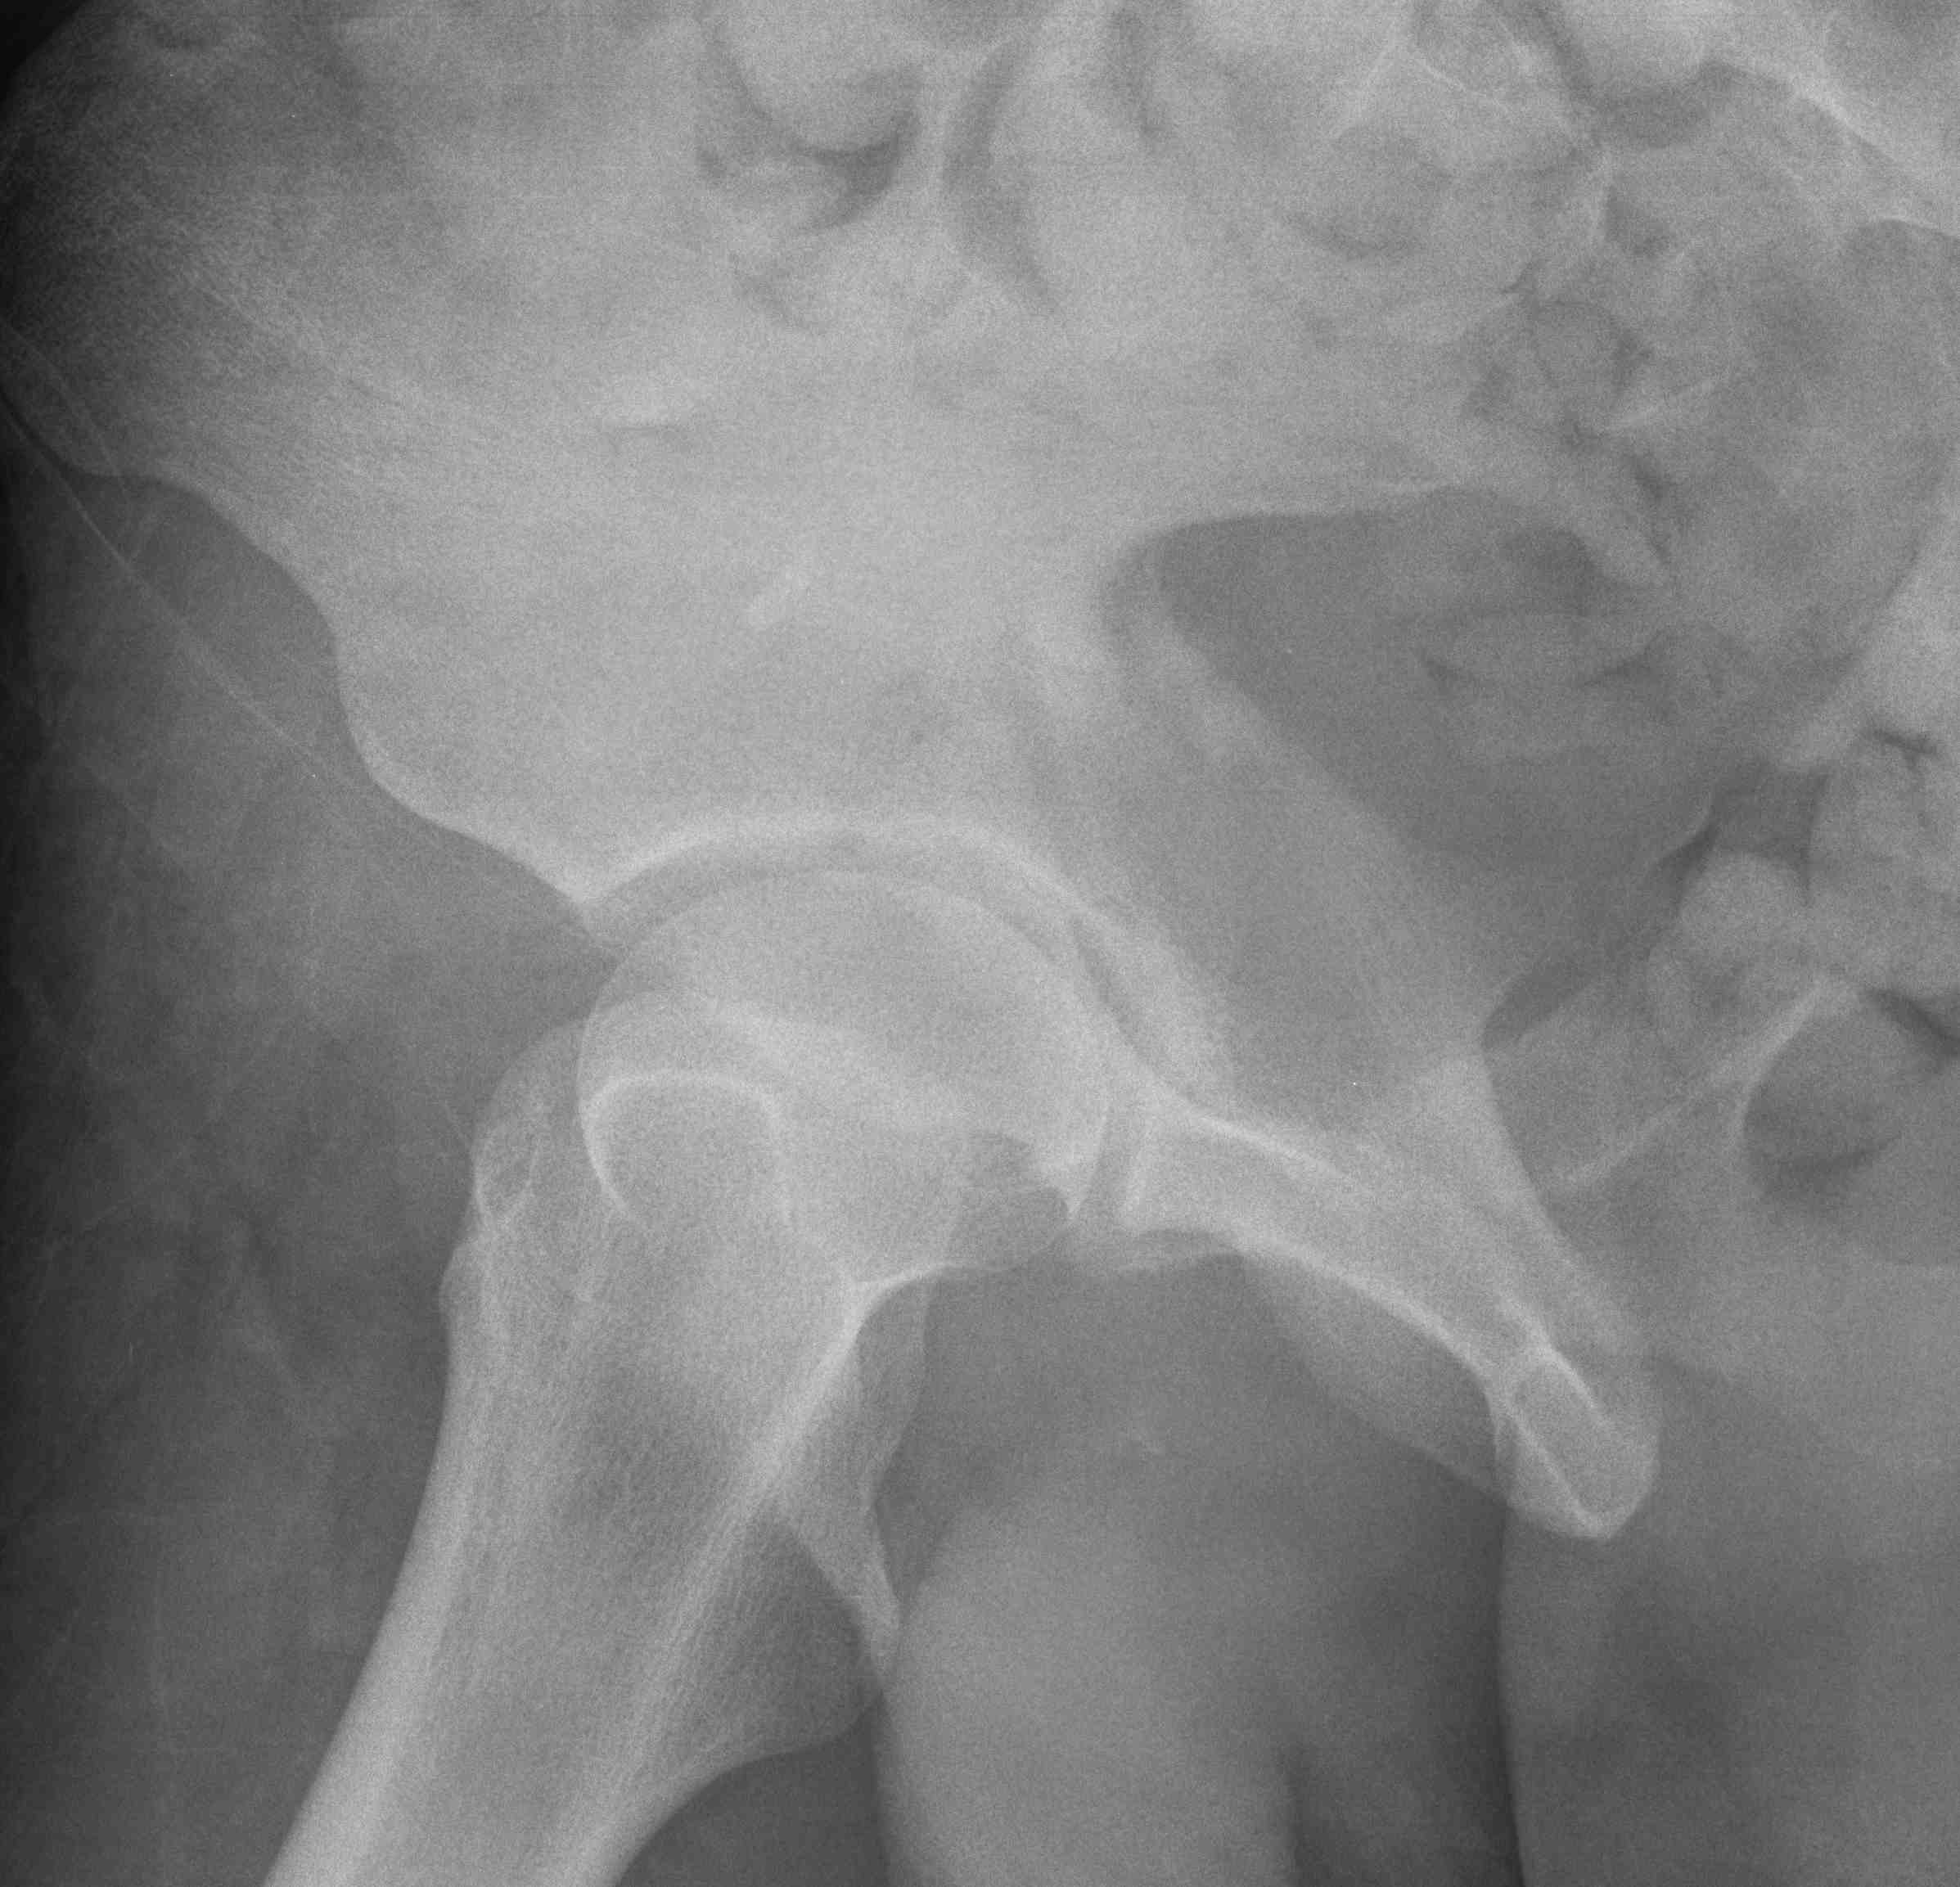

Judet views / 45o obliques

Internal Oblique / Obturator Oblique

- affected side rotated forward

- anterior column + posterior wall

External Oblique / Iliac Oblique

- unaffected side rotated forward

- posterior column + anterior wall